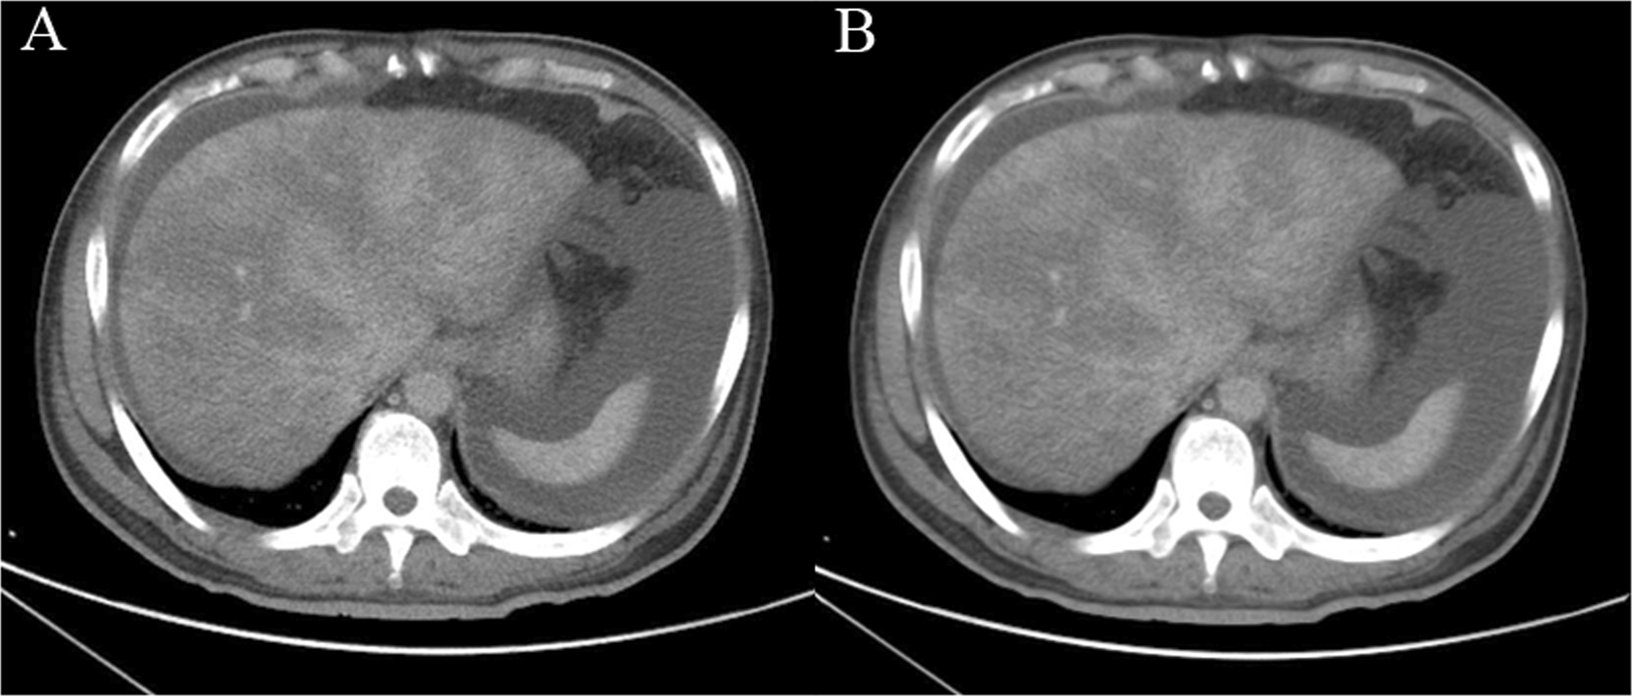

Figure 2

(A) 49-year-old man was diagnosed with PA-SOS and underwent contrast-enhanced CT. CT images were denoised using the anisotropic diffusion method; (A) original and (B) denoised.